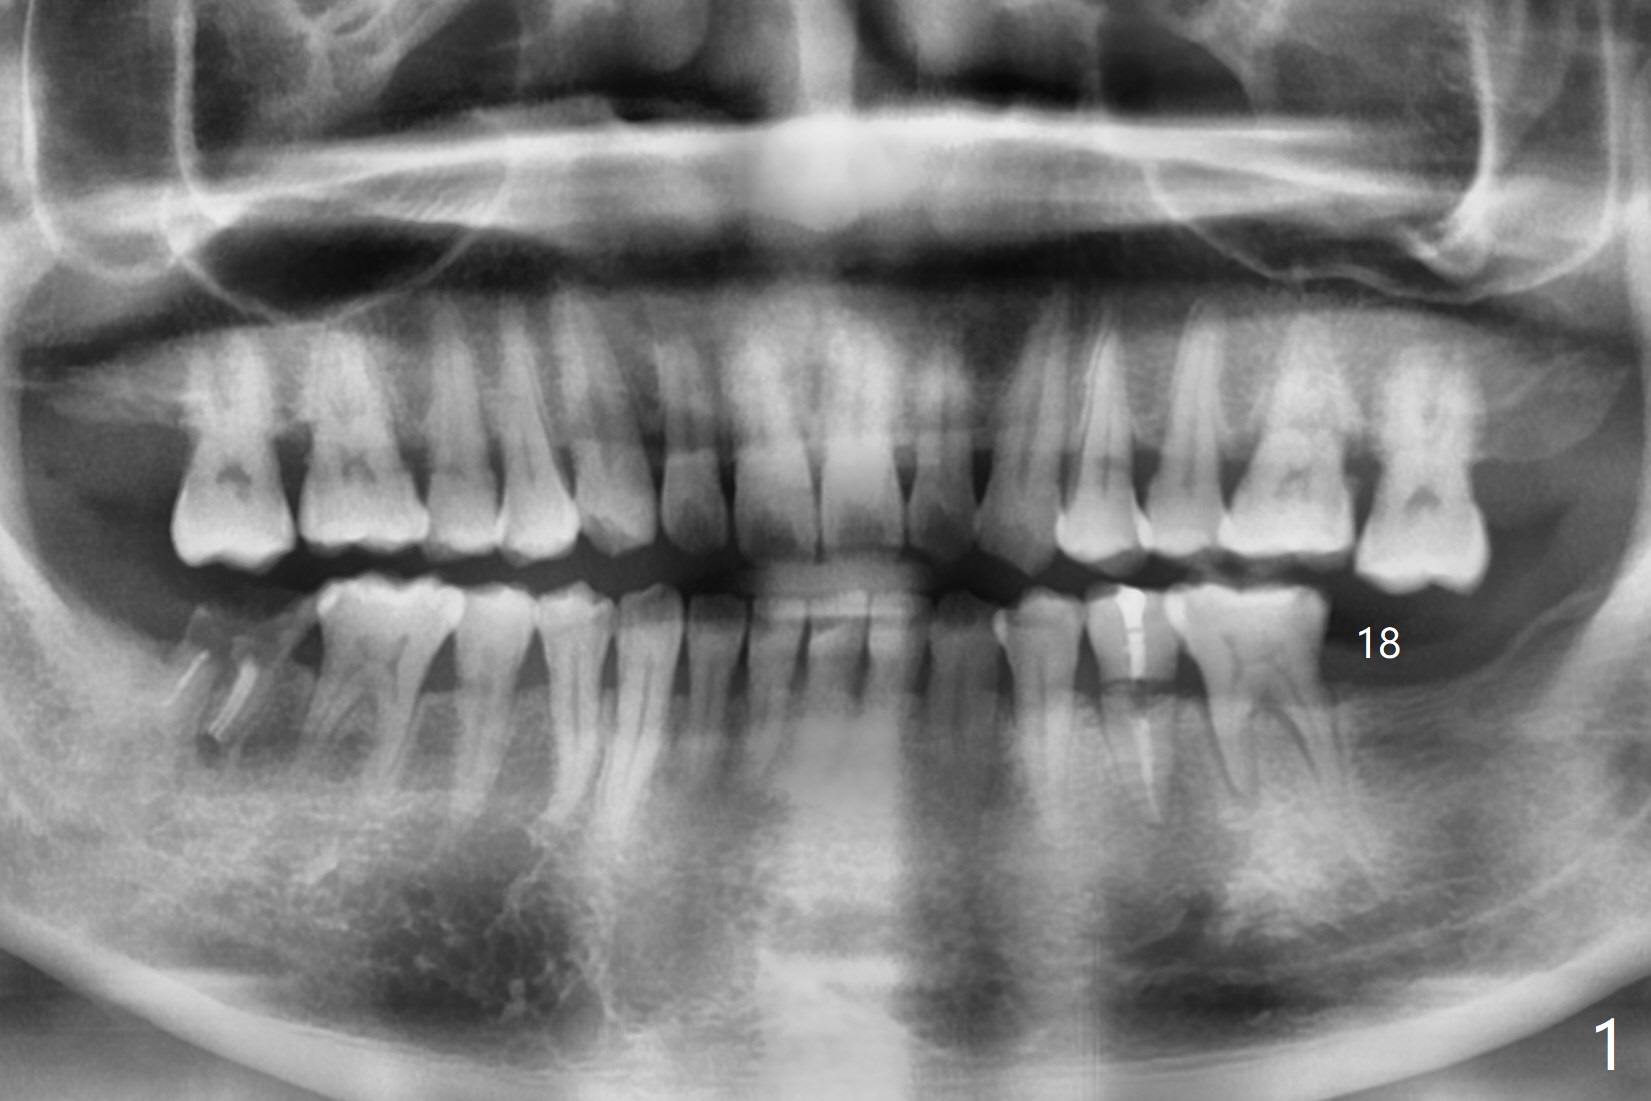

A 40-year-old man with #18 missing and #31 residual roots just fractures the tooth #20 (Fig.1). After discussion, he agrees to have implants at #18 and 20 first. To prevent buccal drifting of osteotomy and implant at #20, the implant will be placed lingual, but it does not contact the lingual plate (Fig.2-4). Traditionally, the whole tooth needs to be extracted (Fig.5,6) before initial osteotomy (Fig.7 red). The latter has tendency to drift buccal because of the lingual slope (Fig.7 arrow). To prevent the drifting, the crown of the tooth is removed (Fig.8). A guide is fabricated with 12 mm offset so that after bone trimmer (Fig.9 pink), the following drills have more contact with metal sleeve. Furthermore the drills will have less chance of buccal shifting because of the presence of the root.